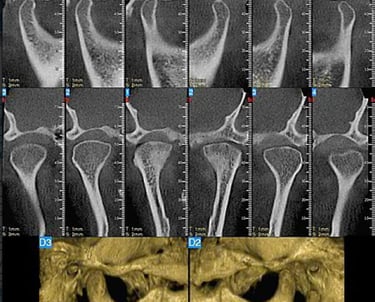

La tomografía computarizada ofrece imágenes detalladas de los huesos de la ATM, útil para identificar anomalías óseas y evaluar fracturas o cambios degenerativos.

Evaluación mediante tomografía computarizada de la ATM